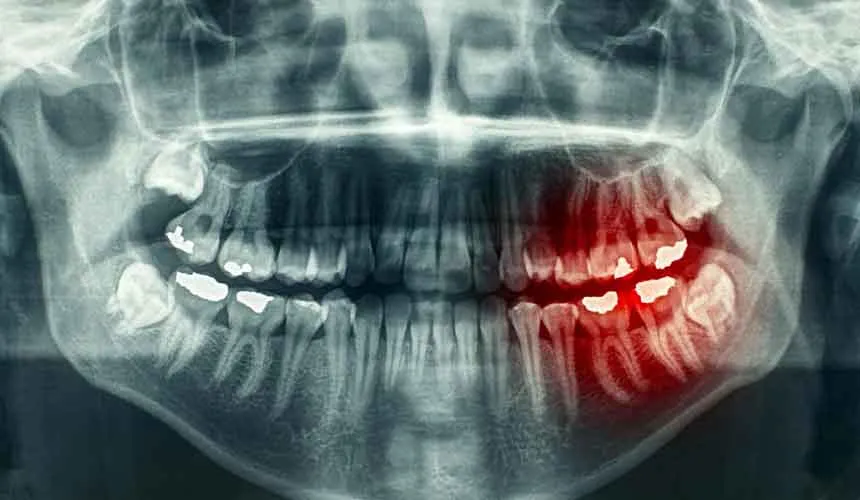

تفسیر نقاط تیره و روشن در عکس های رادیوگرافی

عکس های رادیوگرافی دندان که به آن ها فیلم رادیوگرافی نیز می گویند، از نقاط تیره و روشن زیادی تشکیل شده اند. در تفسیر عکس دندان قسمت های تیره عکس OPG به بافت های نرم دندان گفته می شود که در مرکزیت دندان قرار دارند و پالپ نامیده می شوند. علت روشن بودن این نقاط را می توان امکان عبور آسان اشعه های ایکس از بافت دندان عنوان کرد. اشعه ایکس قابلیت عبور از بافت سخت استخوان یا کلسیفینه را ندارد، به همین دلیل است که عاج دندان ها و ریشه آن ها در عکس OPG به رنگ روشن مشخص می شوند.

علت تیره بودن پوسیدگی ها ی دندان در عکس های رادیوگرافی

در تفسیر عکس دندان با در نظر گرفتن نواحی تیره و روشن و همچنین چرایی وجود چنین کنتراستی، می توان دلیل تیره بودن پوسیدگی های دندان یا همان حفره های دندانی را بهتر درک کرد. پوسیدگی های دندان ها به صورت حفره در ساختار دندان ایجاد می شوند و به این خاطر که بافت دندان ها در این قسمت ها متراکم است، اشعه ایکس مثل بافت های نرم به راحتی از آن ها عبور می کند.

به همین دلیل بخش های پوسیده دندان ها در عکس های رادیوگرافی OPG به صورت تیره نمایش داده می شوند. به عبارت دیگر چون در فرآیند پوسیدگی دندان، محتوای معدنی دندان کاهش پیدا می کند یا به دلیل وسعت پوسیدگی و عمیق شدن آن ها، حفره ها خالی از مواد معدنی می شوند، چگالی بخش های پوسیده کمتر می شود و اشعه ایکس راحت تر در آن نفوذ می کند. به همین دلیل است که در تصاویر رادیولوژی قسمت های خراب دندان ها به صورت نقاط تاریک ثبت می شوند.

نکته مهم در تفسیر عکس دندان در مورد این نواحی تیره آن است که باید هر چه زودتر درمان شوند. چرا که در غیر این صورت این پوسیدگی ها به بافت های نرم و زنده دندان ها به نام پالپ می رسند و باعث عفونی شدن آن می شوند. در نتیجه در اثر عفونت بالای دندان ها، عصب شان تحریک می شود و همین علت اصلی نکروز یا از بین رفتن اعصاب دندان ها می شود. بنابراین لازم است کمرنگ ترین نقاط تیره یعنی نقاطی که کاملا دچار پوسیدگی نشده اند، مورد توجه قرار بگیرند.

روش تشخیص عفونت دندان در عکس رادیولوژی

عفونت یا آبسه دندان به نوعی از عفونت حاد در ریشه دندان ها یا بافت پری اپیکال گفته می شود. در چنین حالتی دندانی که درگیر شده، دردناک می شود و احتمال لنفادناتیک گردن یا تب در بیمار وجود خواهد داشت.

گاهی پوسیدگی ها خبر از آسیب جدی به مینای دندان میدهند. در این صورت باکتری ها وارد پالپ دندان ها می شوندکه ممکن است عفونت پخش شده و ریشه دندان را بیشتر درگیر نماید.

البته ممکن است در 10 روز اول بروز چنین مشکلاتی را نتوان با عکس رادیولوژی تشخیص داد. اما در حالت کلی می توان گفت در تفسیر عکس دندان رادیولوژی ساده پوسیدگی دندان هایی را که عفونت دارند و علائم پوسیدگی آن ها مشخص است را نشان می دهد.